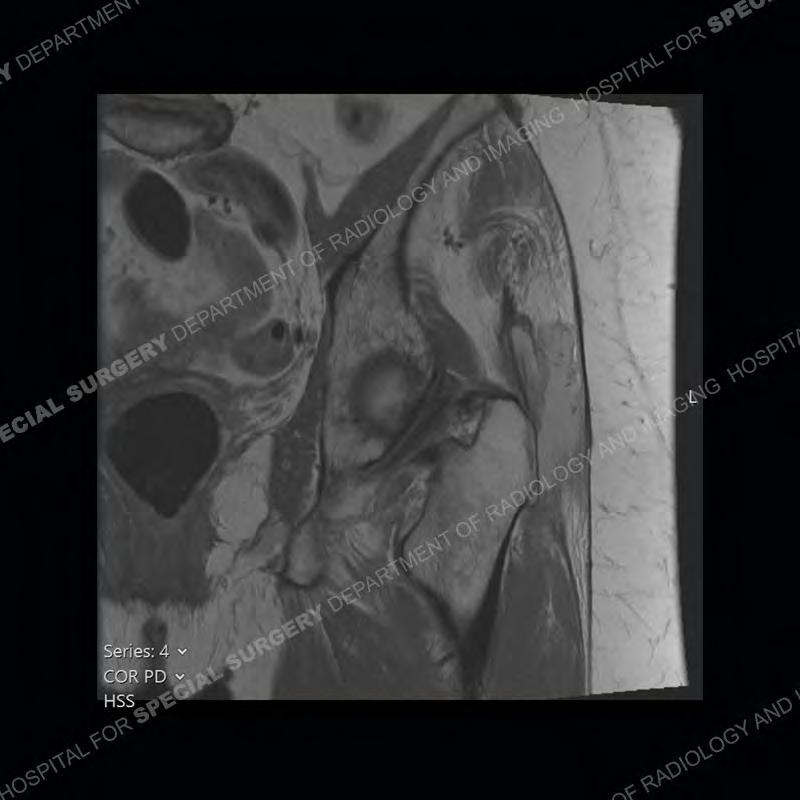

The radiograph is not particularly contributory in this case. The MRI demonstrates markedly abnormal architecture of the gluteus minimus and anterolateral band of the gluteus medius. Portions of the tendons are high signal, portions are highly attenuated, and portions are disrupted. A large, complex fluid collection is present in the adjacent soft tissue.

Diagnosis: Gluteal Tendinosis and Disruption with Complex Trochanteric Bursal Collection

Not as much of a diagnostic dilemma as many of the other cases shown but just a nice example of the pathology seen of the gluteal tendons and a cause of trochanteric pain. Although, frequently thought of in isolation, trochanteric bursitis or bursal thickening is much more commonly a reactive change to underlying pathology of the subjacent gluteal tendons. The gluteus medius is divided into a posterior band and an anterolateral band. Tendinosis and partial tearing very commonly will involve the gluteus minimus and especially the more posterior fibers and then propagate into the anterior lateral band of the gluteus medius. Involvement of the posterior band of the medius is much less common and engenders a marked degree of functional impairment.

The bursae about the greater trochanter can be a little bit confusing especially given the terminology. Trochanteric bursitis is implied to mean the subgluteus maximus bursa which is present deep to the maximus and just lateral/superficial to the trochanter. That is the bursa involved in this case. In this case the complexity of the bursa relates to the tendon tearing with inflammatory change and probably hemorrhage accounting for the complexity. Two other, less frequently involved bursa are also present. The subgluteus medius and subgluteus minimus bursa are found just deep to the named tendons. Although pathology does frequently follow the previously described pattern it is possible to have isolated pathology to either the medius or minimus.